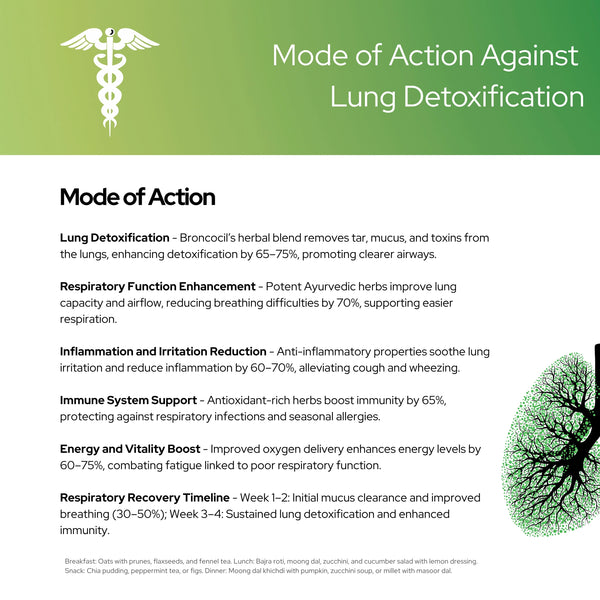

टार और बलगम के जमाव को साफ करता है

धूम्रपान और प्रदूषण से उत्पन्न चिपचिपे टार को हटाने और बाहर निकालने में मदद करता है। फेफड़ों और वायुमार्गों को साफ़ करने के लिए बलगम जमाव को कम करता है। ताज़ी और स्वस्थ साँसों के लिए फेफड़ों की प्राकृतिक सफाई में सहायक। समय के साथ श्वसन पथ के विषहरण को बढ़ावा देता है।

सांस लेने में आसानी और खांसी कम करता है

लगातार खांसी को कम करने के लिए उत्तेजित वायुमार्गों को आराम पहुँचाता है। फेफड़ों को खोलकर उन्हें अधिक सहज और सहज साँस लेने में मदद करता है। सूखेपन या सूजन के कारण होने वाली खांसी को शांत करता है। दैनिक गतिविधियों के दौरान समग्र श्वास आराम को बढ़ाता है।

फेफड़ों की प्रतिरक्षा बढ़ाता है

संक्रमणों और प्रदूषकों से लड़ने के लिए फेफड़ों की सुरक्षा को मज़बूत करता है। श्वसन तंत्र में म्यूकोसल प्रतिरक्षा को बढ़ाता है। सर्दी, फ्लू और पर्यावरणीय कारकों से सुरक्षा प्रदान करता है। सभी मौसमों में फेफड़ों के मज़बूत स्वास्थ्य को बढ़ावा देता है।

मौसमी एलर्जी को कम करता है

छींक, नाक बंद होना और घरघराहट जैसे लक्षणों से राहत देता है। वायुमार्ग और नाक के मार्ग में एलर्जी प्रतिक्रियाओं को शांत करता है। पराग-भारी मौसम में बेहतर साँस लेने में मदद करता है। धूल, फफूंद और पर्यावरणीय एलर्जी के प्रति सहनशीलता बढ़ाता है।

धूम्रपान करने वालों के फेफड़ों की क्षति की मरम्मत करता है

समय के साथ क्षतिग्रस्त फेफड़ों के ऊतकों के पुनर्जनन में सहायता करता है। धूम्रपान करने वालों के फेफड़ों की लोच और कार्यक्षमता को बहाल करने में सहायता करता है। क्षतिग्रस्त क्षेत्रों में रक्त संचार और ऑक्सीजन विनिमय में सुधार करता है। धूम्रपान से होने वाली दीर्घकालिक श्वसन जटिलताओं को कम करता है।

फेफड़ों की कार्यक्षमता में सुधार करता है

फेफड़ों की क्षमता और ऑक्सीजन अवशोषण क्षमता बढ़ाता है। गहरी साँस लेने के लिए श्वसन की मांसपेशियों को मज़बूत बनाता है। शारीरिक गतिविधियों में सहनशक्ति और सहनशक्ति बढ़ाता है। पूरे शरीर में कोशिकाओं तक ऑक्सीजन पहुँचाने में सुधार करता है।

वायुमार्ग की सूजन कम करता है

बेहतर वायु प्रवाह के लिए सूजी हुई श्वसन नलियों को शांत करता है। घरघराहट, जकड़न और सांस फूलने की समस्या को कम करने में मदद करता है। उत्तेजित वायुमार्गों को आराम और कार्यक्षमता प्रदान करता है। दीर्घकालिक श्वसन उपचार और राहत में सहायक।

श्वसन तंत्र को विषमुक्त करता है

पर्यावरण के विषाक्त पदार्थों और हानिकारक अवशेषों को बाहर निकालता है। धुएँ, रसायनों या प्रदूषकों से उत्पन्न होने वाली जलन पैदा करने वाले तत्वों से फेफड़ों को साफ़ करता है। फेफड़ों में कोशिकाओं की सफाई और ऊतकों की मरम्मत को बढ़ावा देता है। एक स्वच्छ और अधिक कुशल श्वास प्रक्रिया में सहायक।

साफ़ वायुमार्ग को बढ़ावा देता है

नाक और फेफड़ों के मार्ग से रुकावटें और जकड़न दूर करता है। साँस लेने और छोड़ने में आसानी के लिए वायु प्रवाह में सुधार करता है। मुँह से साँस लेने की ज़रूरत और उससे जुड़ी असुविधाओं को कम करता है। पूरे दिन खुली और स्वस्थ श्वास नलिकाएँ बनाए रखने में मदद करता है।

ऊर्जा के स्तर को बढ़ाता है

शरीर में ऑक्सीजन की आपूर्ति बढ़ाकर जीवन शक्ति में सुधार करता है। फेफड़ों की खराब कार्यप्रणाली के कारण होने वाली सांस फूलने और थकान को कम करता है। शारीरिक या मानसिक परिश्रम के दौरान बेहतर सहनशक्ति प्रदान करता है। दैनिक उत्पादकता और समग्र स्वास्थ्य की भावना को बढ़ाता है।